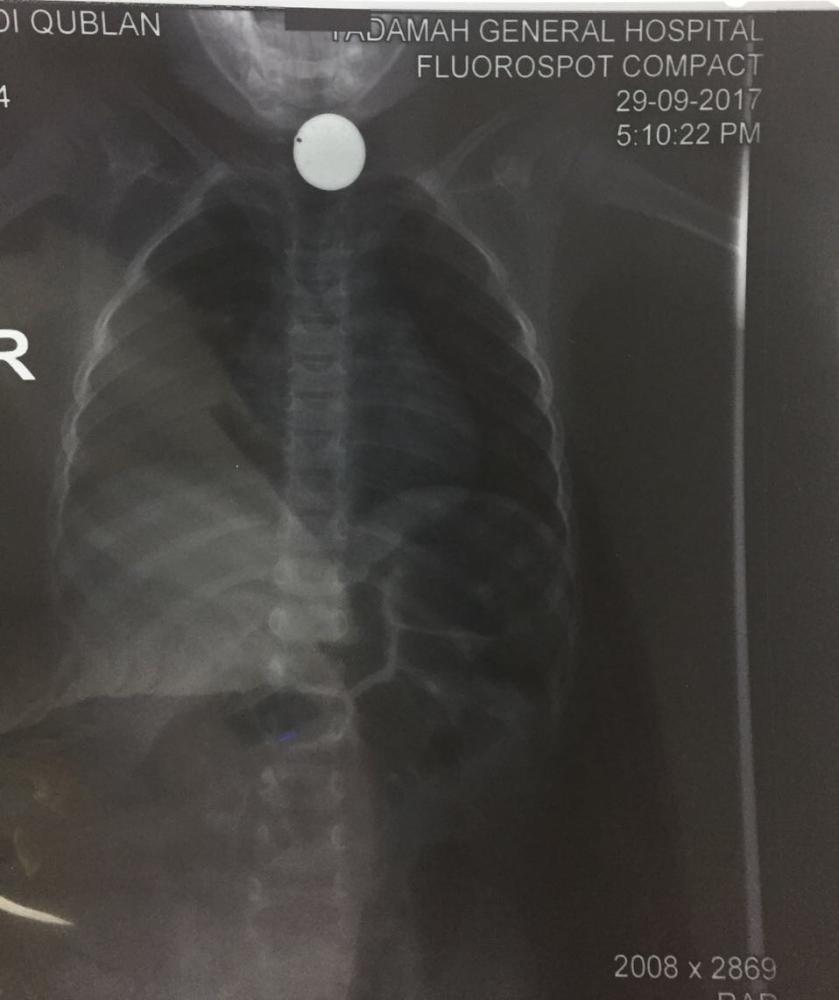

في الوقت الذي لا تزال فيه حوادث إبتلاع الأطفال للقطع المعدنية والأجسام الغريبة تتكرر، أستقبل قسم الطوارئ بمستشفى الولادة والأطفال بنجران طفل يبلغ من العمر 3 سنوات تم إحالته وإسعافه من أحد مستشفيات المنطقة، وهو يعاني من صعوبة بالتنفس وكثرة اللعاب بسبب إبتلاع جسم غريب، وعلى الفور تم إجراء الفحوصات اللازمة والتي أظهرت بالأشعة وجود جسم غريب بالمرئ. وطبقا لمعايير حقوق المرضى تم شرح الحالة لوالد الطفل والخطة العلاجية لاستخراج الجسم الغريب مع أخذ موافقته على إجراء منظار عاجل، وبفضل الله وتوفيقه نجح الفريق الطبي من استخراج الجسم الغريب (قطعة معدنية) بحجم 2 سم، مما ساهم في استقرار حالة الطفل في الوقت نفسه أكدت صحة نجران على ضرورة الوقاية وحماية الأطفال من التعرض لابتلاع الأجسام الغريبة، مما يعرض حياتهم للخطر، كما دعت صحة نجران أولياء الأمور الانتباه وحفظ الأشياء الصغيرة بعيدا عن متناول الأطفال الصغار، تجنباً لأي مضاعفات قد تؤدي للوفاة جراء بلعها أو استنشاقها.